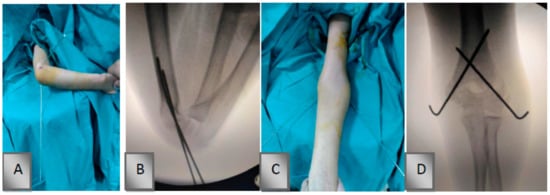

2.1. Surgical Technique